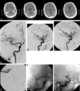

Arterial branch occlusion

Central retinal artery occlusion (CRAO) is a disease of the eye where the flow of blood through the central retinal artery is blocked (occluded). There are several different causes of this occlusion; the most common is carotid artery atherosclerosis. [Source: Wikipedia ]